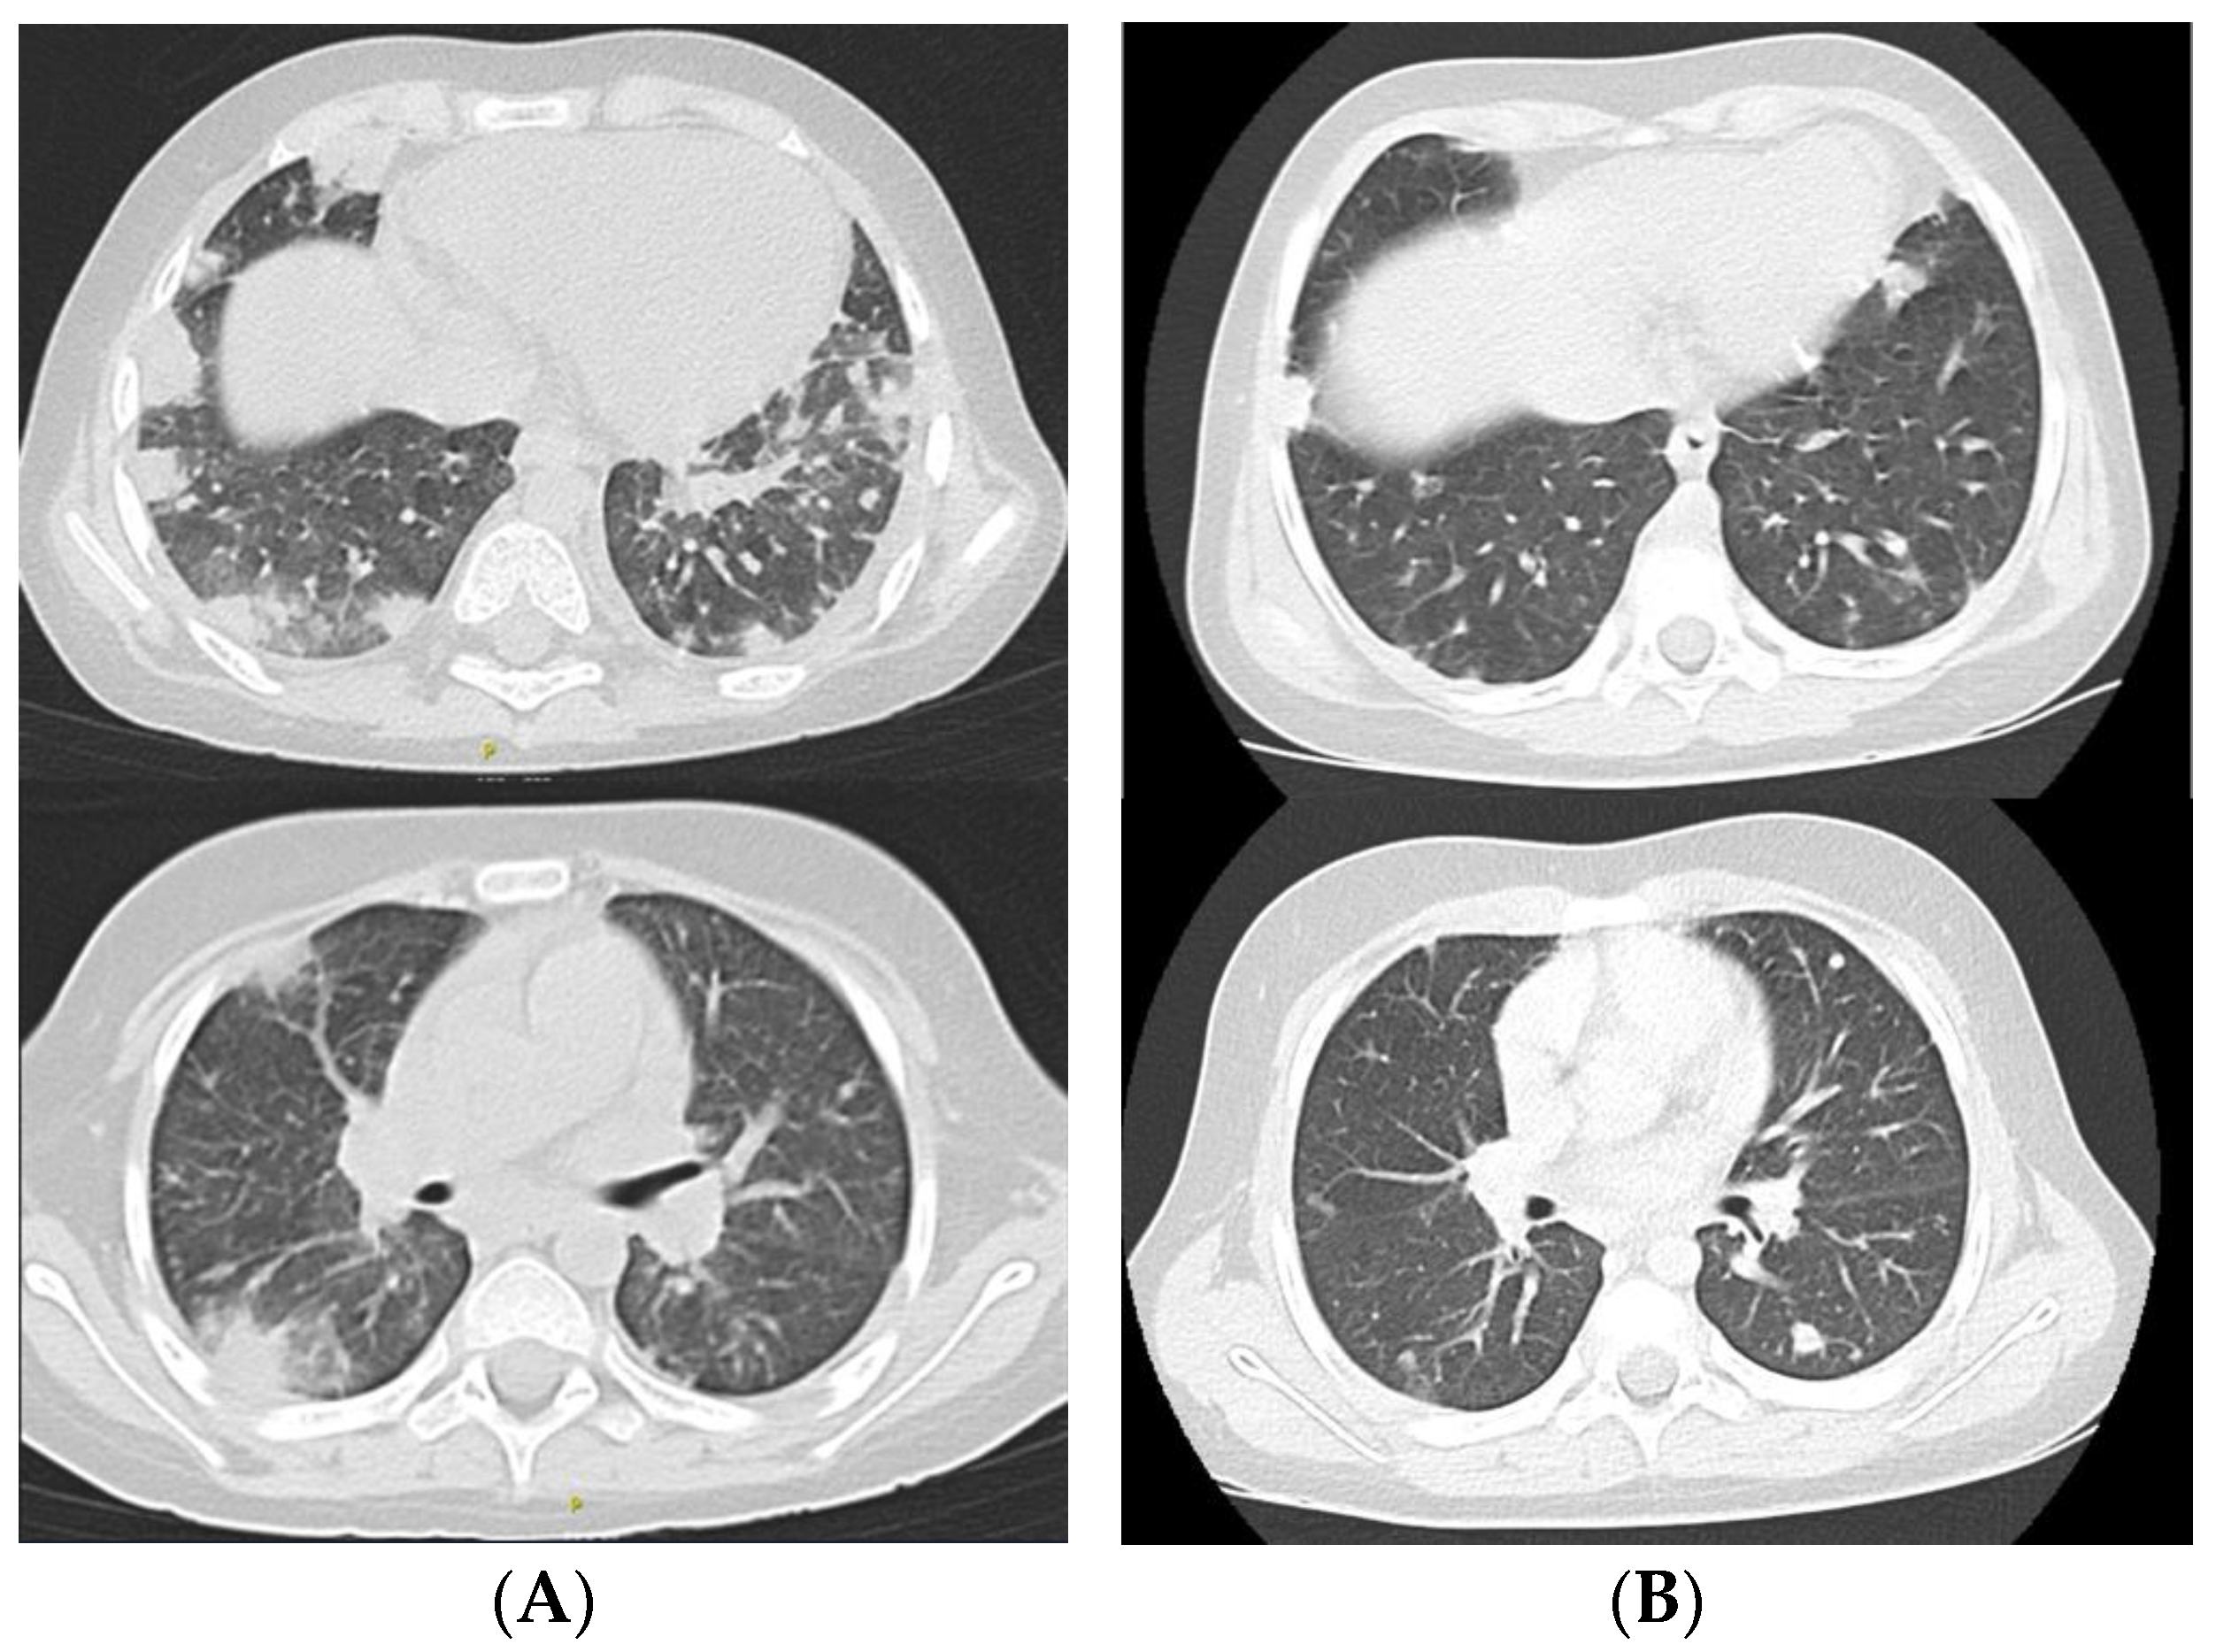

3.1. The First Episode of Infection

3.3. The Second Episode of Infection